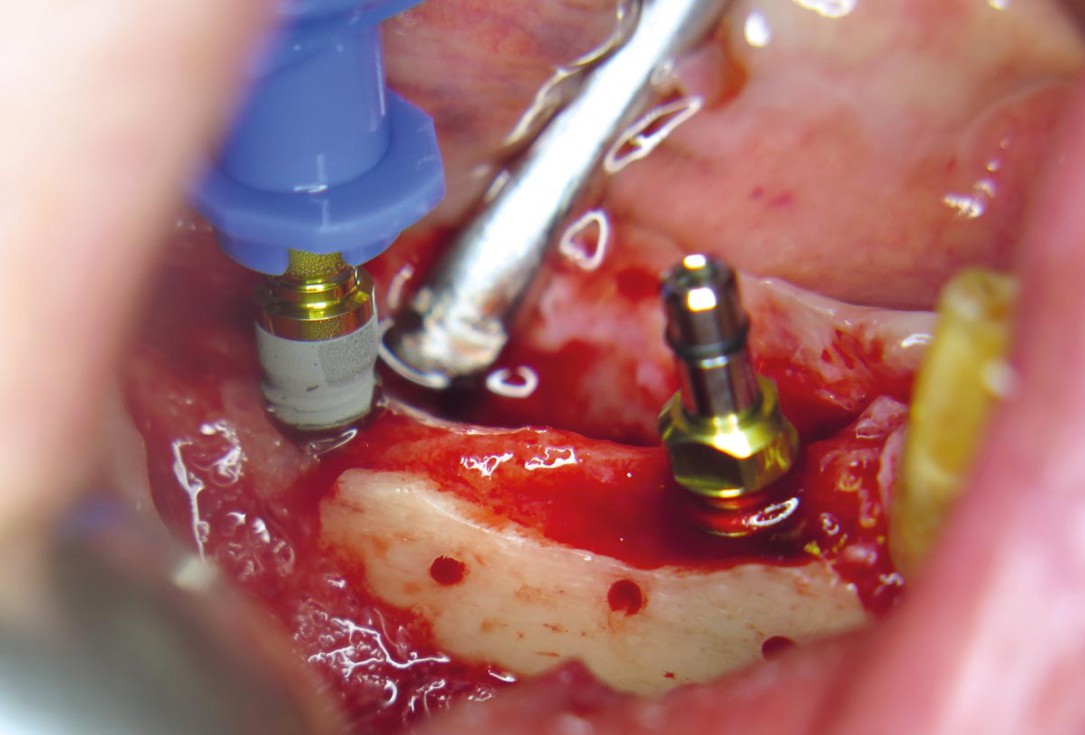

11 / 20 - Insertion of two dental implants in regio 44 and 46Horizontal ridge augmentation with maxgraft® cortico - M.Sc. E. Kapogianni